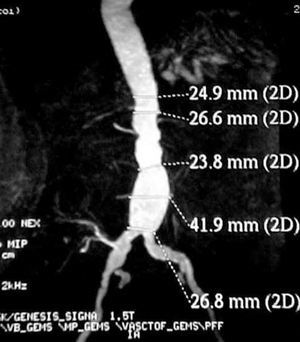

Contrast-enhanced computed tomography (CT angiography) provides high-resolution images and the possibility of 3-dimensional reconstruction. It is the technique of choice in the diagnosis and the preoperative study. The aortoiliac anatomy, the characteristics of the wall (inflammation, calcification, signs of rupture, thrombus), the visceral vessels and anatomical variations (horseshoe kidney, left renal vein, or left IVC) can be evaluated in detail (Figure 1). The disadvantages are the radiation and the use of a contrast agent. Contrast-enhanced magnetic resonance (MR) has the same properties as CT angiography, but eliminates the risk of nephrotoxicity and ionizing radiations (Figure 2). The degree of stenosis in visceral vessels may be overestimated, it does not detect calcifications and it produces artifacts in individuals with steel implants. However, in the follow-up of endoprostheses made of nitinol, MR angiography has been found to be useful in the detection of leaks.31-33

Figure 2. Image of an abdominal aortic aneurysm obtained with magnetic resonance angiography in a renal transplant recipient (right iliac artery). (Image courtesy of Dr I. García of Hospital Valdecilla, Santander, Spain.)